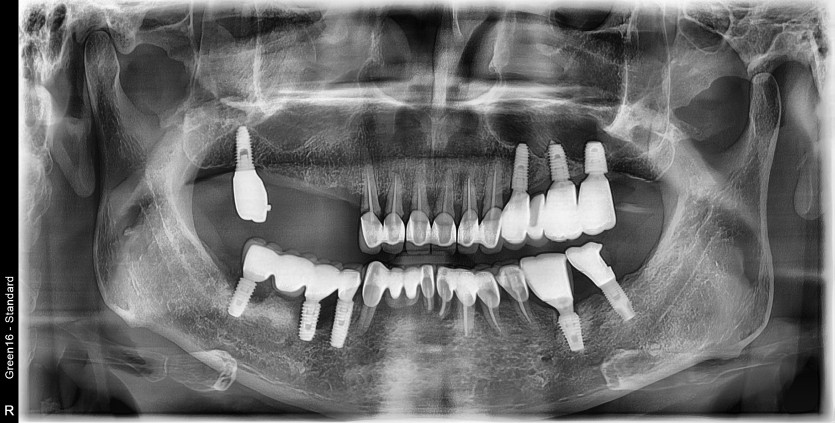

#44.45.46.47 타원 임플란트 보철물 제거 후

임플란트 재수술+치조골 이식술 시행하였습니다.